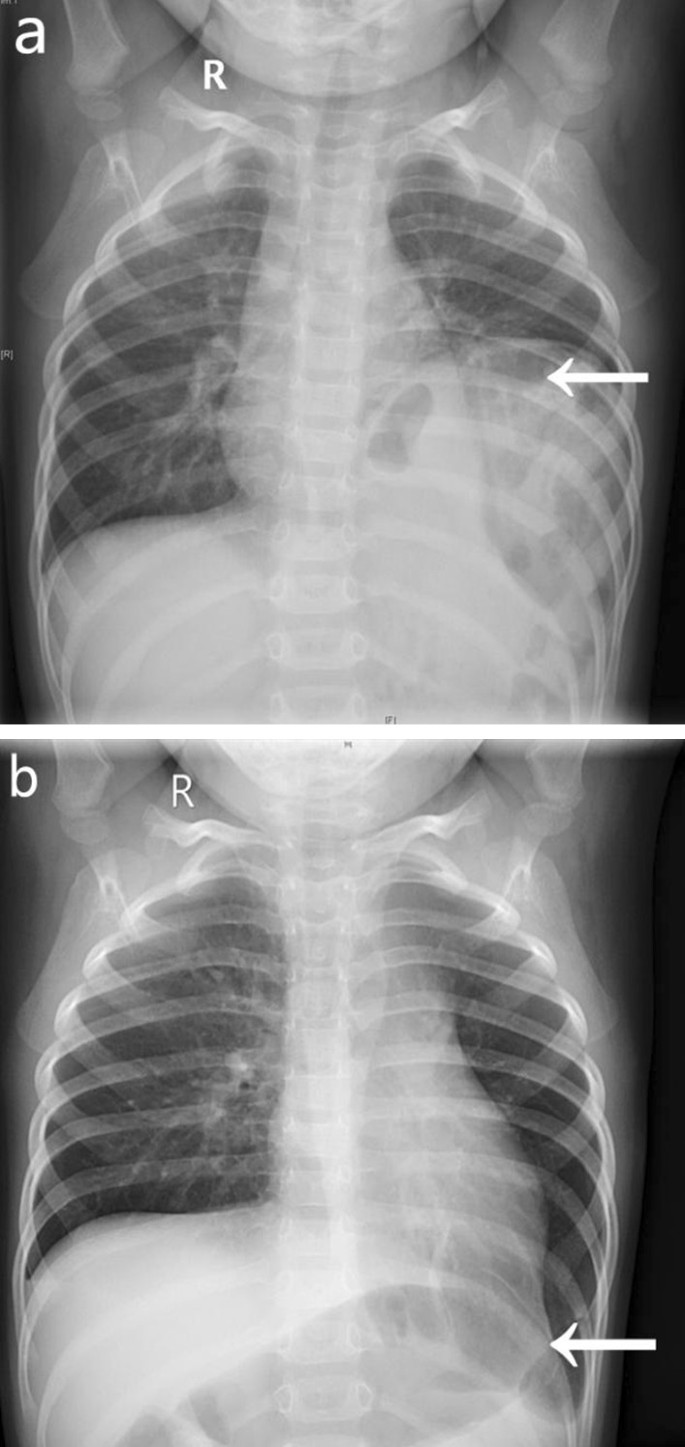

Place one hand on your abdomen and breathe deeply. Reduced number of alveoli air sacs required for normal breathing. In severe cases when there is no simple treatment that can relieve dyspnea your doctor may prescribe morphine. Congenital diaphragmatic hernia CDH. There is usually a long history of heavy smoking. Shortness of breath may be accompanied by wheezing. Diaphragmatic dysfunction caused by transverse myelitis or leukemic infiltration of the cervical spinal cord in a patient with leukemia and shortness of breath. To treat phrenic nerve irritation This condition can be managed with a breathing pacemaker which takes over the responsibility of sending messages to the diaphragm. The cause for shortness of breath was thought primarily due to stable angina on tread mill test positive finding but Chilaiditis syndrome should also be considered as a cause for the shortness of breath.

The rise in intraabdominal pressure further increases intrathoracic and lung volume by pushing the lower rib cage outward. In severe cases when there is no simple treatment that can relieve dyspnea your doctor may prescribe morphine. Diaphragmatic dysfunction caused by transverse myelitis or leukemic infiltration of the cervical spinal cord in a patient with leukemia and shortness of breath. Diaphragmatic plication a surgical procedure that pulls the diaphragm down by introducing a repeated series of continuous sutures across the diaphragm and pulling the muscle taut. A bedside fan or open window with a breeze are also simple but very effective treatments to lessen dyspnea. Depending on the severity of injury to the diaphragm some doctors recommend non-surgical options to treat the breathing issues associated with diaphragm weakness and paralysis. P E Pulmonary embolism.